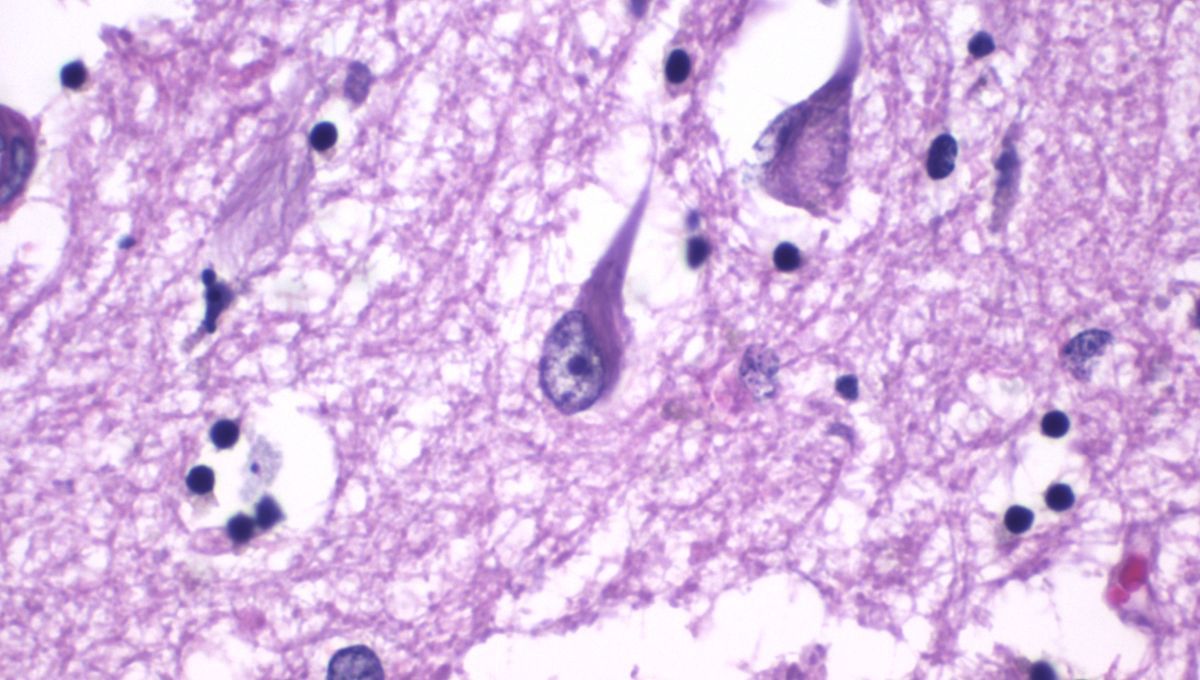

Alzheimer’s-Linked Protein Levels “20 Times Higher” In Newborn Babies – What Does This Mean?

We spoke to the first author of a new study that could challenge much of what we thought we knew about Alzheimer’s disease.